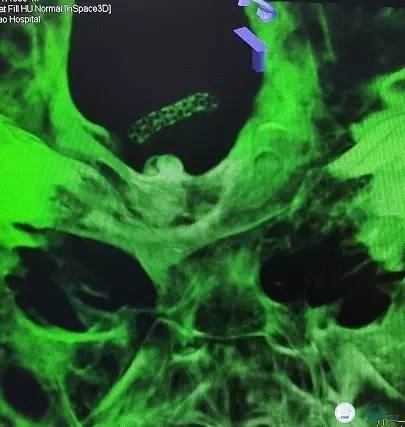

头颈部CTA(图3-6):双侧椎动脉远端及基底动脉近端混合斑块、管腔中-重度狭窄,双侧大脑后动脉纤细。

图3

图4

图5

图6